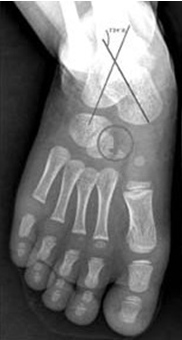

Each patient was subjected to antero-posterior and stress dorsiflexion lateral view of feet and talocalcaneal, talo-first metatarsal angle and tibio-talar angles were measured. Anteroposterior view was taken by placing the foot flat on X-ray plate and tilting the tube 30 degrees from the vertical plane. Stress dorsiflexion lateral view was taken by forceful dorsiflexion at midfoot level [Table/Fig-2].

Diagrammatic representation of radiological angles in antero-posterior(AP) and stress dorsi-flexion lateral view.

Pre Ponseti treatment Talo Calcaneal angle of 35 degrees in antero-posterior radiographic view.

Pre Ponseti treatment Talocalcaneal angle of 18 degrees in stress dorsiflexion lateral radiographic view;

Post Ponseti treatment Talocalcaneal angle of 33 degrees in AP view;

Post Ponseti treatment Talo calcaneal angle of 28 degrees in stress dorsiflexion Lateral view.